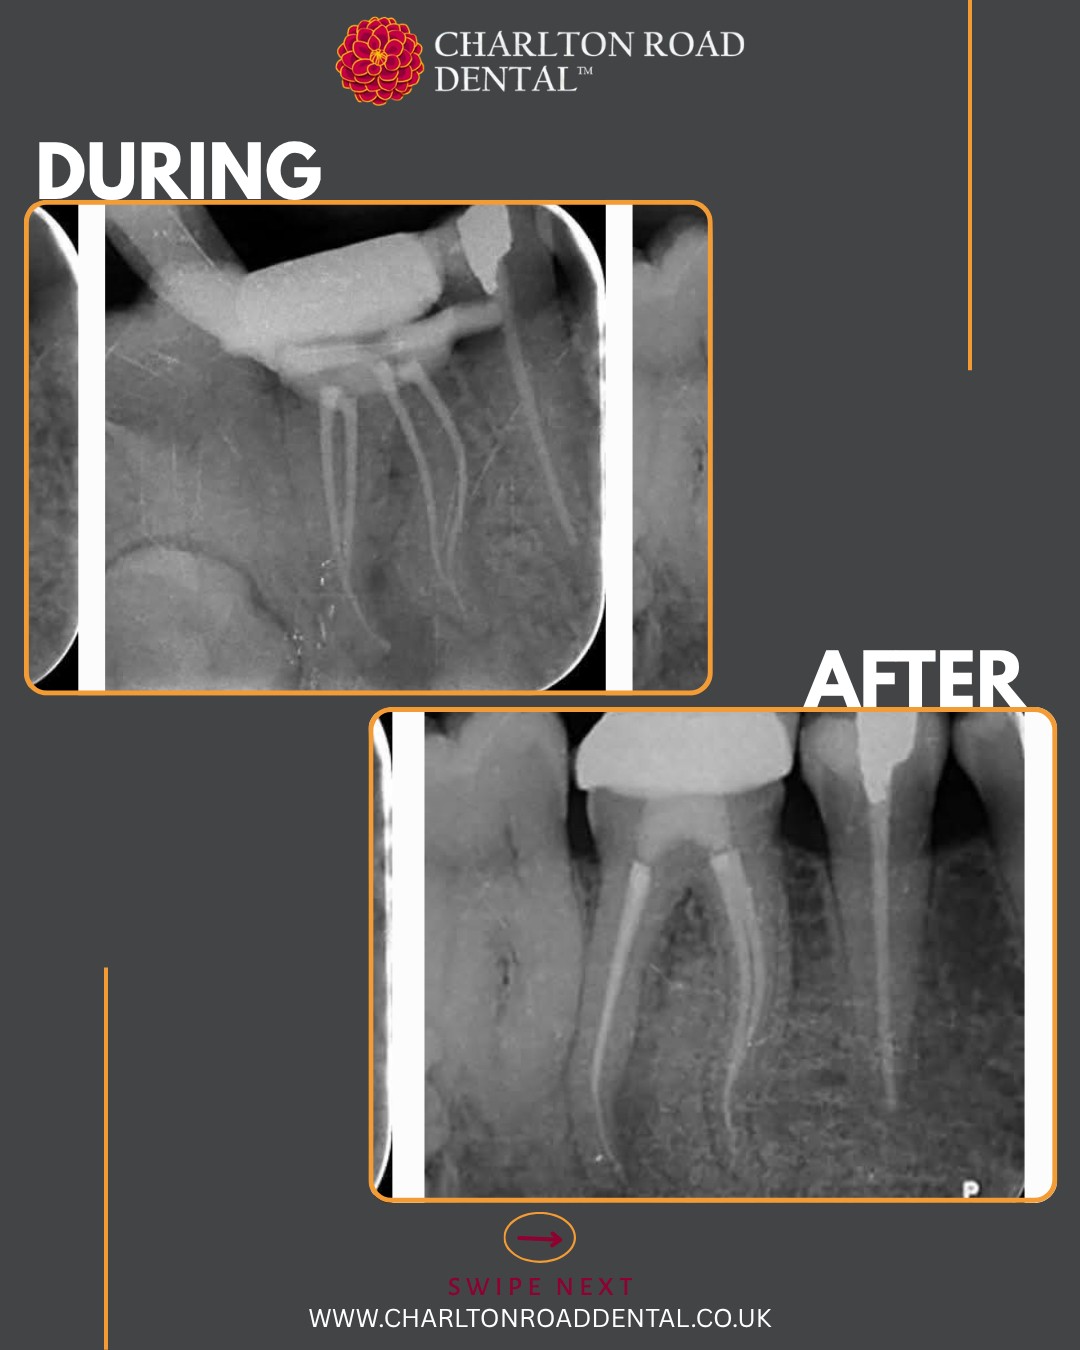

A complex RCT case by Dr. Adrian Jones

S-shaped curves in molar canals are ideal for putting the VS Flexi Blue files to the test. These files offer excellent flexibility and allow for conservative shaping of the canals, thereby preserving precious tooth structure.

First up: a UL6. Periodontal treatment has been completed and stabilised. This was a necrotic case with a history of an acute flare-up a few months ago. I used the existing filling as a reference to help orient the access cavity. Numerous pulp stones were encountered.

I prepared the DB and palatal roots first, allowing the MB root to soak in disinfection solution in the meantime. I instrumented the MB root system up to size 20/06, and up to 25/06 in the palatal and DB roots. Irrigation was performed using full-strength sodium hypochlorite and Endo solution, delivered with Irriflex tips. I used a yellow EndoActivator for agitation and micro-suction to dry the canals.

Total Fill sealer was placed and carried to working length using a size 25/029 gutta-percha point. I customised a size 20/029 GP point for the MB root, a 25/029 GP point for the DB root using a taper plate, and used a master fit GP point for the palatal root. The tooth was then sealed with LuxaCore.

Each tooth is as unique as a fingerprint, so a flexible, hybrid approach was taken to cleaning and preparing the canals prior to obturation.